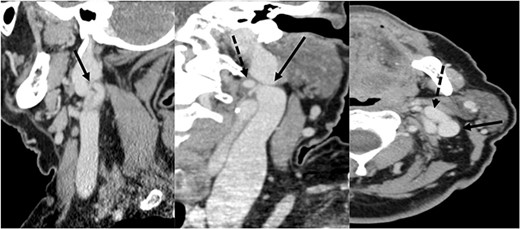

A 72-year-old woman underwent total laryngectomy + thyroid isthmectomy + bilateral (II–IV) laterocervical dissection for a G3 SCC of the right hemilarynx (involving the right true and false vocal cord and extending to the anterior commissure and left vocal cord). The preoperative radiology report did not mention any IJV variations. Nonetheless, a left IJV fenestration was observed in the preoperative study, raising the suspect of a possible SAN variant (Fig. 3). Pathological stadiation of the patient was pT4a (infiltration of thyroid cartilage and prethyroid soft tissue) pN2c, cM0. Intraoperatively, the fenestration of the left IJV, that was noticed during the CT, was confirmed. As for the first patient presented, the SAN nerve passed medially to the anterior vein and laterally to the posterior vein (Fig. 4).

CT scan showing the fenestration of the IJV; left image: sagittal section showing the fenestration (arrowhead) of the left IJV; central image: coronal section showing the anterior (dotted arrowhead) and the posterior (arrowhead) part of the fenestrated IJV; right image: axial section showing the anterior (dotted arrowhead) and the posterior (arrowhead) part of the fenestrated IJV.